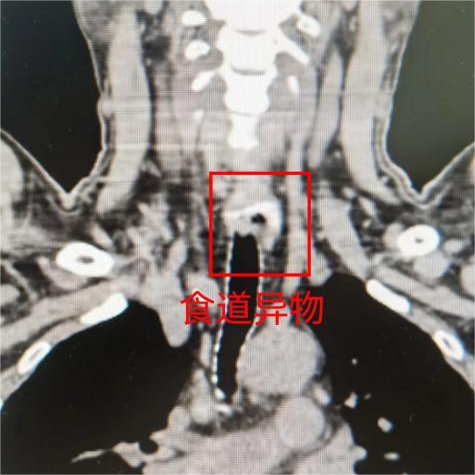

经相关检查,医生发现是一块排骨卡在了龚先生的食管入口处,需进行手术。手术中,医生成功从龚先生的食管入口处取出了一段长达5厘米的排骨,并为其进行了食管瘘修补。